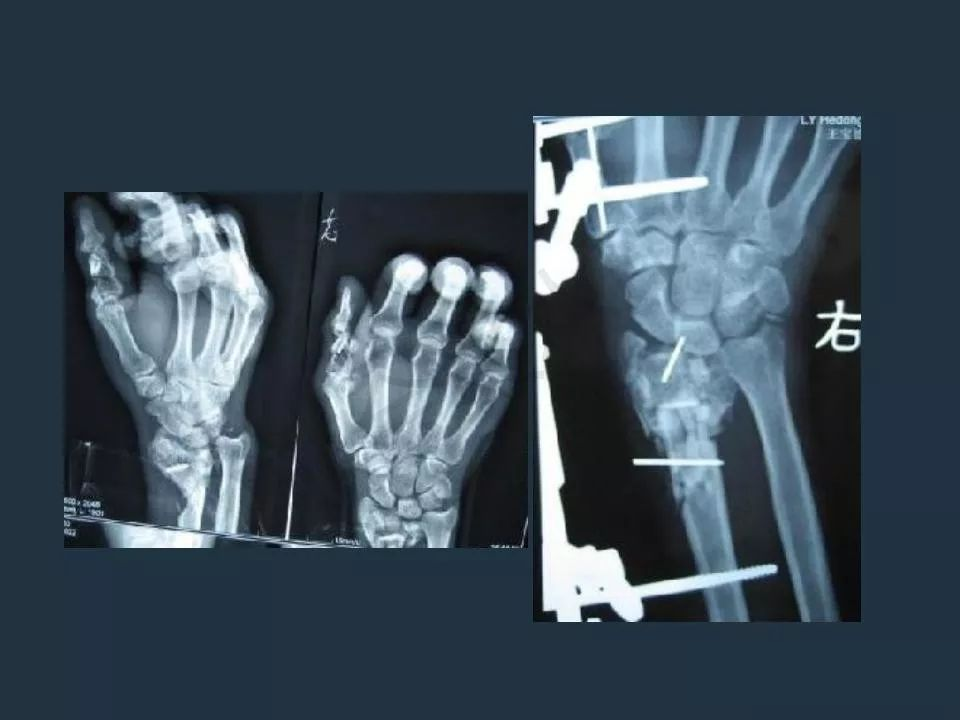

外固定支架技术治疗急诊骨折

骨科外固定支架

骨科外固定支架掌指骨架